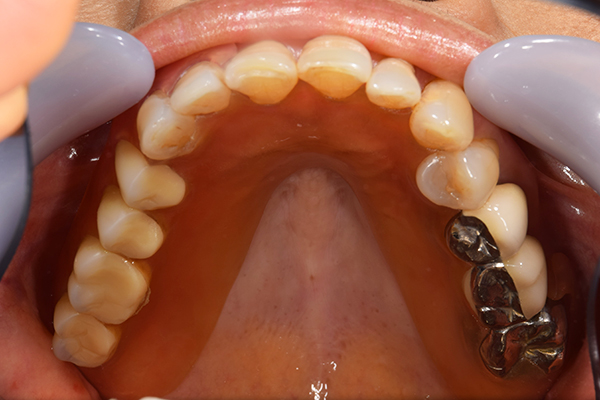

ケース2(自費の総入れ歯と部分入れ歯)

上下の入れ歯が外れやすくなったということでいらっしゃいました。 顎の骨はしっかりしていましたので、精密な型取りさえすればしっかりした入れ歯がつくれると思いました。 また下には6本歯が残っていましたが、虫歯になっている歯もありました。 かぶせ物のなかで大きな虫歯があった歯があり、1本だけ残せない状態でした。

上の入れ歯は確かに吸着は甘くなっていました。 また下の入れ歯はバネの一部が壊れており、安定感がなくなっていました。

精密な型取りの後、噛み合わせのチェックをしていきました。 かぶせ物も同時に作っていきました。

歯を並べた後、かぶせ物のフレーム作ってもらいました。先に歯を並べて理想の位置を決めておくことが大切です。

完成した入れ歯とかぶせ物です。 入れ歯への寛容度が高い患者様でしたので、 金属は使用せず、プラスチックのみで上は仕上げました。 下顎も歯は1本減ってしまいましたが、しっかり 入れ歯が維持できる様な構造にしました。

お口の中に入れた状態です。 見た目も最初とほとんど変わることなく作成できました。 維持や吸着に関しても問題ないようでした。

年齢 80歳・女性

主訴 上下の入れ歯が外れやすくなった

治療期間 3ヶ月

治療費 .メタルボンドクラウン:550,000円

.義歯:990,000円(税込、上下)

治療方針 長年使ってきた義歯の人工歯が磨耗し、臼歯部での咬合がすくなくなり、入れ歯の安定も悪くなり、あたりどころが悪くなって痛みが出ている。 そのため、入れ歯を上下作りかえる必要がある。

治療内容 過去に治療を行ったことのある歯が再度虫歯になってしまっているところがあり、すでに残せない状態にまでなっていたため、歯を一本抜歯した。 その後、かぶせ物と入れ歯を同時に作成していった。

特記事項 歯を抜いた後は、2〜3ヶ月歯ぐきの回復を待ってから入れ歯を作るため、待機期間があります。その間、古い入れ歯を調整しながらそのまま使うか、新し物をつくっておく必要があります。ただし、入れ歯は保険治療で作成する場合、6ヶ月は新しいものが作れないという決まりがあるので保険で全て作りたい場合は注意が必要です。